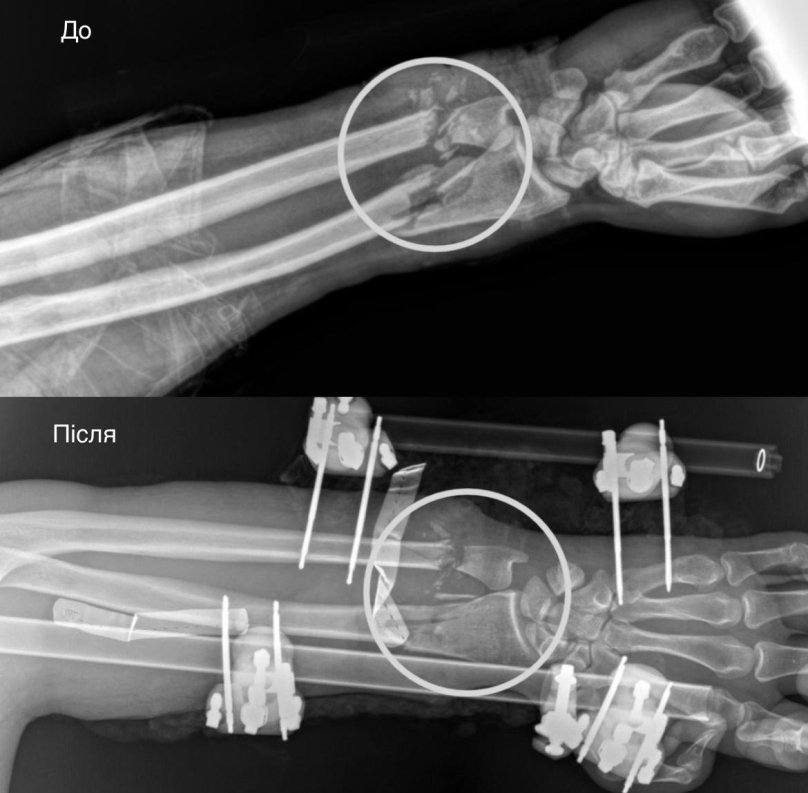

На Львівщині чоловік різав дрова бензопилою та відрізав собі руку. Внаслідок цього, рука чоловіка трималася на клаптику шкіри та могла бути фактично ампутованою. Про цей випадок повідомили у четвер, 26 лютого, у Першому медоб’єднанні Львова.

Як стало відомо, 37-річний мешканець Львівщини заготовляв дрова та в одну мить бензопила вислизнула йому з рук і майже перерізала повністю ліве передпліччя. Дружина чоловіка швидко наклала імпровізований джгут із тканини й викликала медиків. Потерпілого одразу доправили до Львова у лікарню святого Пантелеймона та розпочали невідкладну операцію.

У чоловіка була критична травма, що включала повністю пересічені артерії, пошкоджені кістки, сухожилля, м’язи та нерви. Відтак, рука трималася на шматку шкіри.

«Складність оперативного втручання полягала у відновленні всіх структур і, по суті, самої функції руки. Без відновлення кровопостачання рука була б нежиттєздатною і довелося б виконувати ампутацію. Лише злагоджена поетапна робота мультидисциплінарної команди дала шанс її зберегти», — пояснює завідувач відділення судинної хірургії Андрій Мелень.

Медикам вдалось зберегти кінцівку чоловіку. Зараз він проходить тривалу реабілітацію, у нього поступово відновлюється чуття пальців. За словами медиків, є шанс на повне відновлення функцій руки.